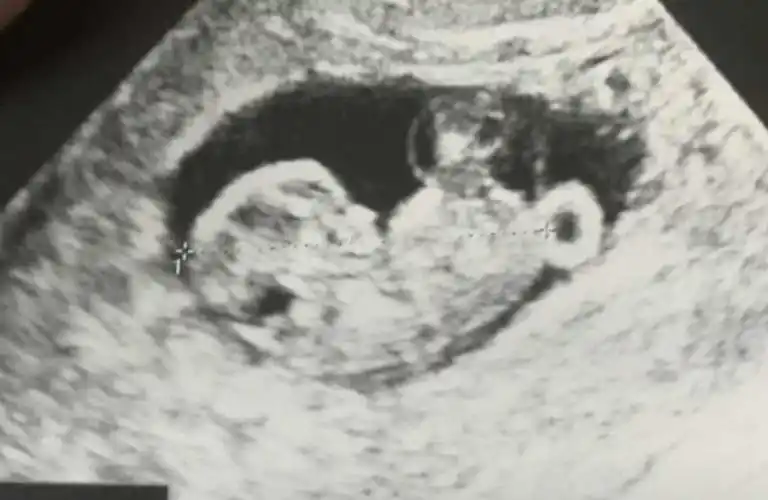

杜若溪确认怀孕严屹宽生日爆宝宝b超照鼻子超挺